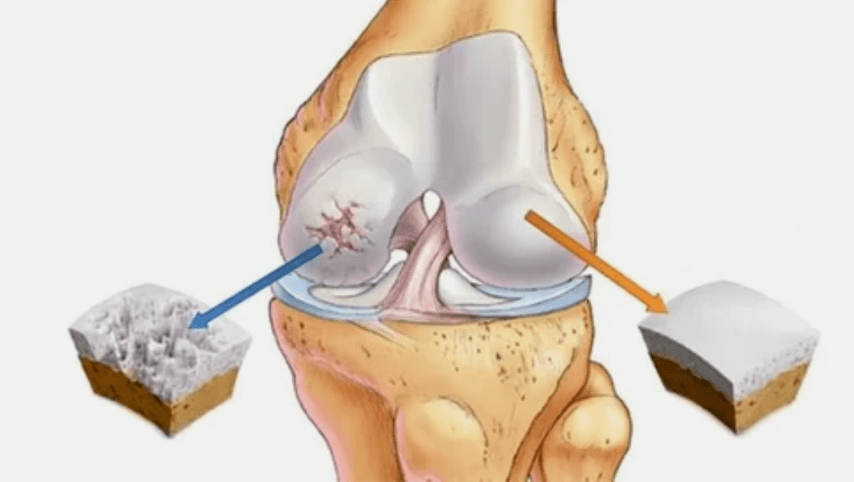

- The primary lesion affects the hyaline cartilage.In case of circulatory disorders, pathological power deterioration occurs.It is the first step or cause, which may occur arthrosis.

- Hyalin coating pathologies.The thinning of the cartilage leads to the replacement of its pathological tissues - bone structures.

- Anomalous growths appear on cartilage - osteophytes.

- The arising violation of the natural anatomy of the cartilage and bones provokes the overload of healthy areas of cartilage.The destruction of articular tissues without treatment is constantly progressing and lead to disability.

When the degree of disease increases, pathological processes are still aggravated.In the end, all hyalin cartilage is destroyed.